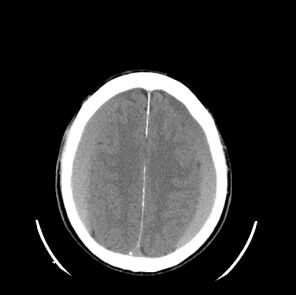

74.78歲女性,主訴一週以來步態不穩且頭痛。未注射顯影劑的頭部電腦斷層影像如圖,最可能的診斷為何? (A)bilateral subarachnoid hemorrhage (B)bilateral meningioma (C)bilateral subacute epidural hematoma (D)bilateral subacute subdural hematoma